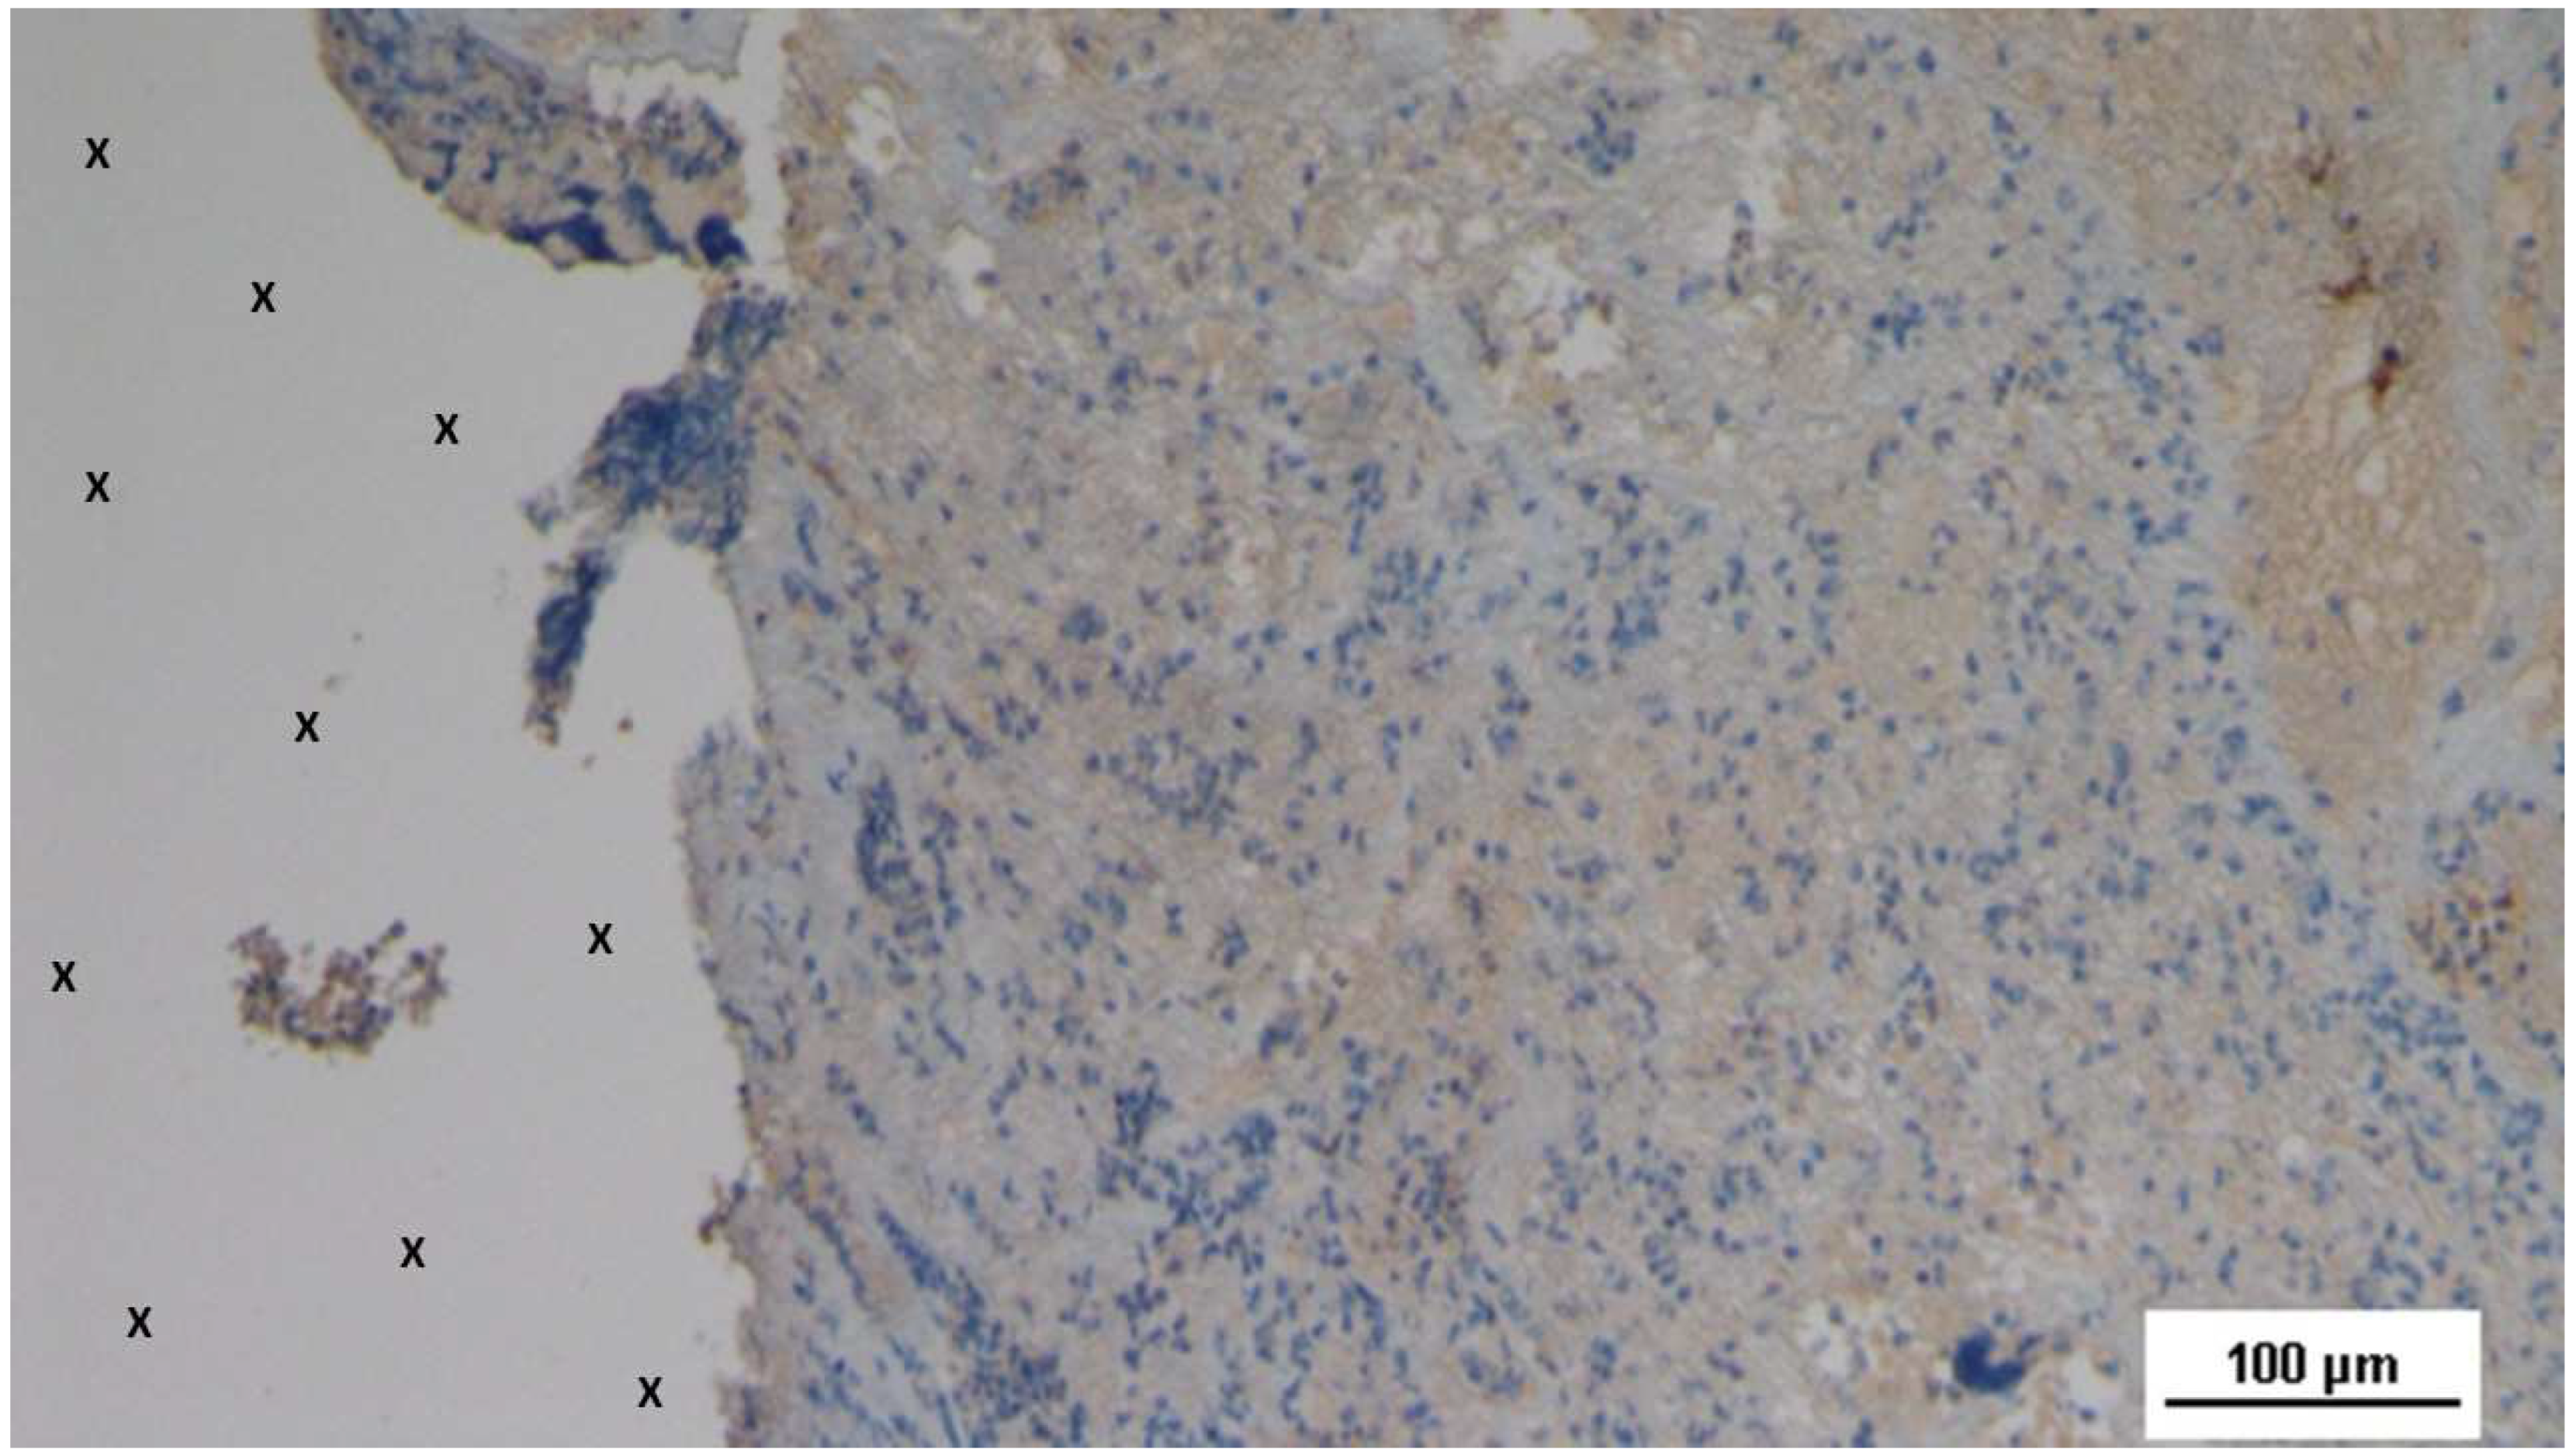

In the early post-implantation period (Short-term, ST), the neurogenic growth factor NGFRp75, which is critical for nerve formation, was observed in limited quantities throughout the S&S Hernia System structure (Figure 21).

Figure 21. Biopsy specimen excised 4 weeks post-implantation (Short term - ST). NGFRp75-positive cells (beige/brown staining) are evident near the TPE fabric of the 3D scaffold (X). NGFRp75 100X.